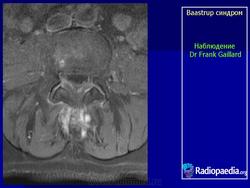

"Бааструпа (Baastrup) болезнь, osteochondrosis interspinalis, arthrosis interspinal, kissing spine, описана в 1932 г. Характеризуется наличием хронических воспалительных изменений в остистых отростках позвонков. Вследствие этого возникают длительно удерживающиеся боли в поясничном отделе позвоночника, особенно при чрезмерном изгибе его кзади или чрезмерной нагрузке (поднимание тяжестей), с местной болезненностью в области остистых отростков. На рентгенограмме видны расширенные остистые отростки со склеротическими краями, иногда на верхнем или нижнем крае отростка остеофиты, которые могут даже соприкасаться между собой. Этиология-врожденное, неправильное развитие остистых отростков поясничных позвонков; заболевание наблюдается в определенном возрасте (30-40 лет) и у людей определенных профессий (грузчики).

Следует учитывать и относительную частоту неоартроза между остистыми отростками - межостистый диартроз (Meyer Н., 1924), «целующиеся отростки» (BrailsfordJ., 1929; Baastrup С, 1933). Синдром Бааструпа может сопровождать межпозвонковый остеохондроз (Forrai J., Tannai J., 1962). Е.С.Заславский и соавт. (1973) среди больных поясничным остеохондрозом определяли клинические и рентгенологические признаки синдрома Бааструпа в 5,5%. Боли при данном синдроме по характеру тупые, ноющие, сверлящие. Они усиливаются после длительного сидения, переноски тяжестей, при разгибании туловища. Выявляются болезненность и ограничение подвижности позвоночника (особенно в позе разгибания) на уровне пострадавших двигательных сегментов, болезненность при пальпации соответствующих межостистых промежутков. При вызывании феномена вибрационной отдачи в области поясничных межостистых связок боли, как правило, не только усиливаются, но и иррадиируют в пределах скле-ротома: в крестец, ягодицу, бедро. Инфильтрация же 1-2 мл 1% раствора новокаина межостистого промежутка быстро снимает эти феномены. Синдром связывают с поясничным гиперлордозом, структуральным сколиозом, переломом и вывихом позвонков, деформирующим спондилезом с аномальным увеличением остистых отростков. С.А.Рейн-берг (1964) относил изменения остистых отростков при данном синдроме к явлениям патологической перестройки костной ткани, обусловленной нагрузками чрезмерной силы на задние отделы позвоночного столба. Согласно N.Fellmann (1964), формирование сустава между остистыми отростками проходит следующие стадии: межостистый остеосклероз, фасетирование и склероз, тяжелое артрози-рование, анкилоз.

Рисунок 1